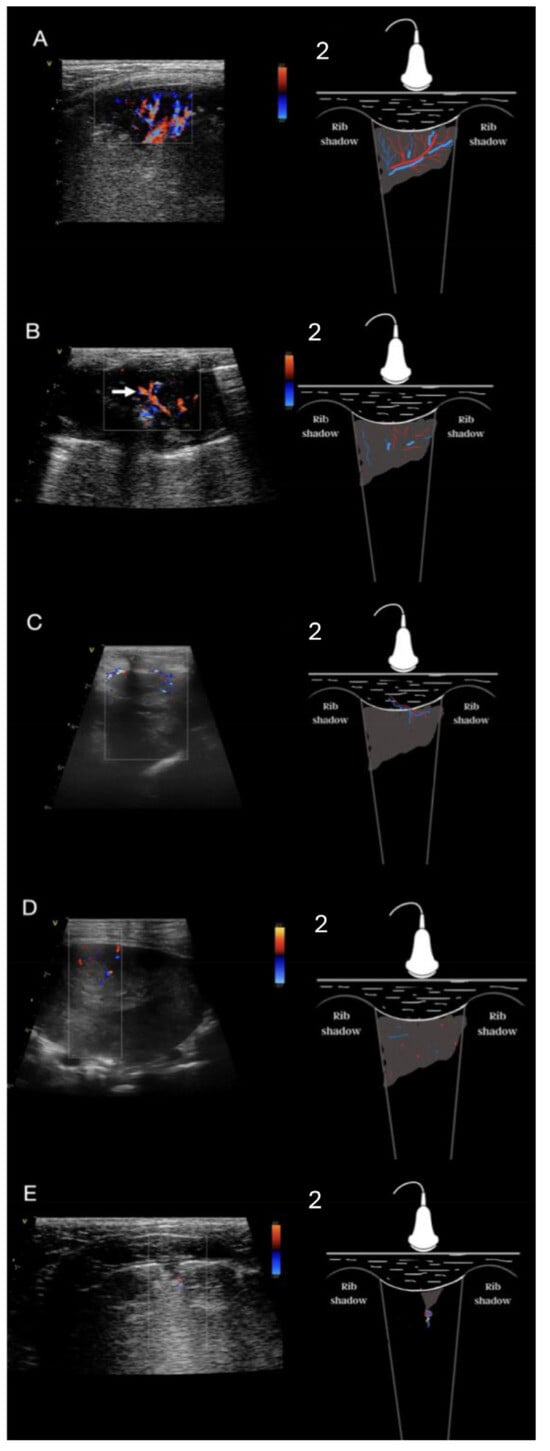

2.5. Analysis of Consolidations in Color/Power Doppler Mode

3.4. Analysis of Vascularity